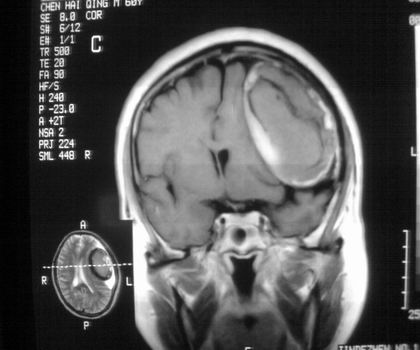

以下是引用影像孺子牛在2008-4-29 21:20:00的发言:[br]首先病变定位在脑外,根据ct密度及mri信号特征考虑慢性硬膜下血肿不连续环形钙化。

以下是引用周战梅在2008-4-29 23:12:00的发言:[br]脑外病变,蛛网膜下腔增宽,囊壁点状、环形钙化,增强扫描呈不均匀环状强化,考虑为囊性脑膜瘤可能性大,慢性脓肿、血肿机化、胆脂瘤不能除外。